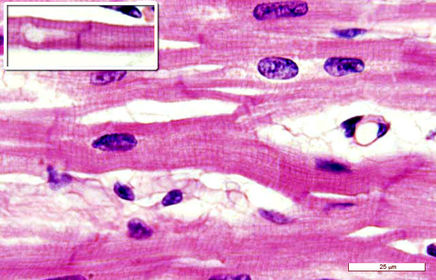

Tejido muscular (cardíaco) con estriaciones núcleos visibles